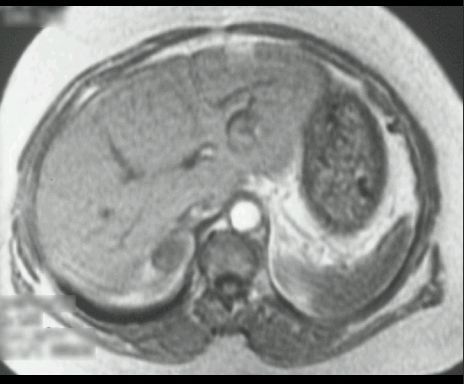

GRUCZOLAK NADNERCZA

MR